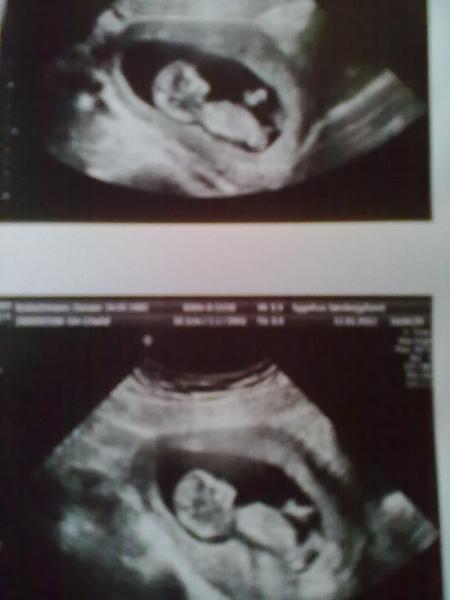

Hi Mädels Heute war der grosse tag des Ultraschalles und der Nackenfaltmessung und mein Freund war mit was mich sehr freute, und er hat augen gemacht als er sah wie unser Krümel rum gehüpft ist. Also mein Krümel hat sich sehr gewehrt da gegen das es gemessen wird, ich sollte den bauch rum ruckeln und hüpfen damit er sich mehr hin legt und nicht sitzt, es sahs auf eine vene von mir und das polsieren der Vene fand es sehr bequem . Na ja nach dem 2. mal hüpfen von mir hat er mich doch glat mehrmals getreten und das ende vom lieb war das ich Montag nochmal kommen soll da es nicht möglich war die Nackenfalte zu messen, d.h. nochmal bilder für mich am Montag Bericht vom Krümel: Mein Krümel ist jetzt schon 5,7cm lang von kopf bis po und ich wurde wieder vorgesetzt ich bin jetzt in der 12+0 Jippi und der Et ist der 24.07

hier mit fuss

alle 2 zusammen